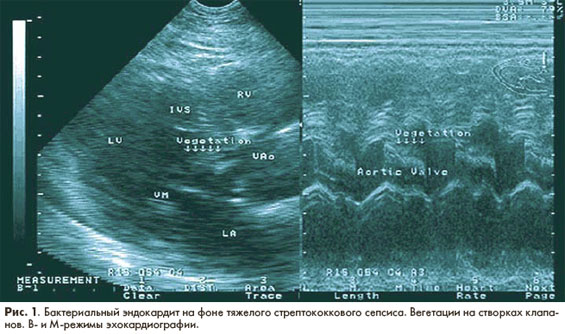

Достоверным и доступным в клинической практике критерием эффективности антибактериальной терапии ИЭ является исчезновение в ее результате вегетаций на клапанах и других структурах эндокарда при ультразвуковом исследовании сердца. На рис. 1, 2 представлены результаты ультразвукового исследования пациента (собственное наблюдение) со стрептококковым сепсисом, потверждающие высокую эффективность монотерапии тейкопланином.

результаты ультразвукового исследования  пациента со стрептококковым сепсисом